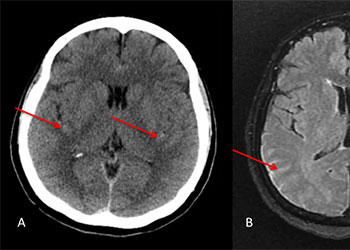

MRI with contrast is the usual diagnostic as the enhancement and bright signal on T2-weighted imaging reveals spinal cord venous congestion from inappropriate arterial input. Both endovascular embolization and microsurgical clipping are relatively safe and effective treatment with the degree of recovery correlated with the duration and severity of symptoms. It is my practice to attempt embolization as the first line of therapy. If this is either not accomplished or the fistula is not closed significantly and clinical symptoms persist as happens on occasion, surgical ligation is performed.